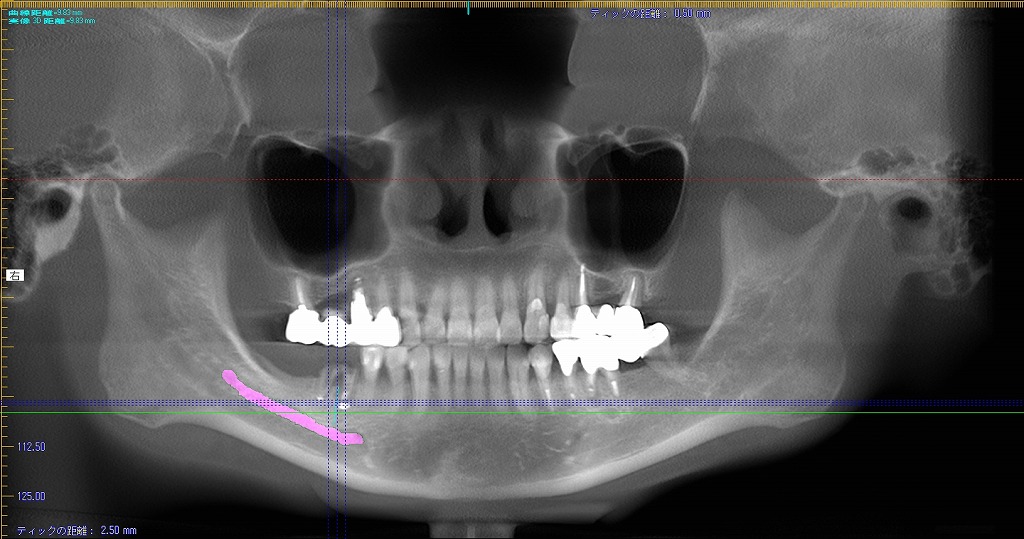

埋入位置にインプラント窩を形成していきます

今回は神経までの距離がないケースなためここが1番のシビアな部分になります

埋入窩を形成しそこにばーを差し込み距離を測ります

埋入前と埋入後のパントモになります

神経までの距離がないことがうかがえます